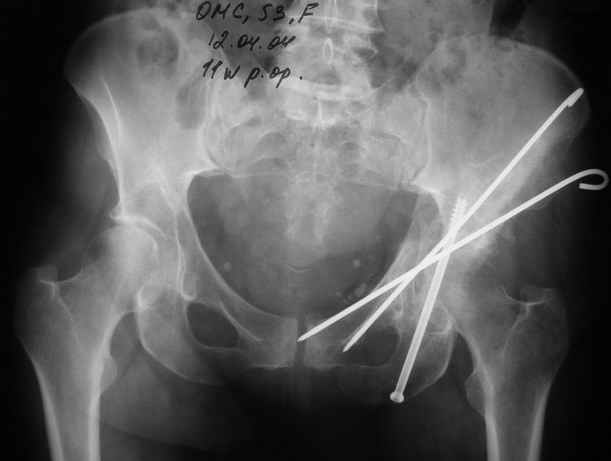

Еще раз спасибо за комментарии и готовность помочь с имплантами. Постоп картинки в приложении,

27.01.04

02.02.04

10.02.04

12.04.04

02.06.04